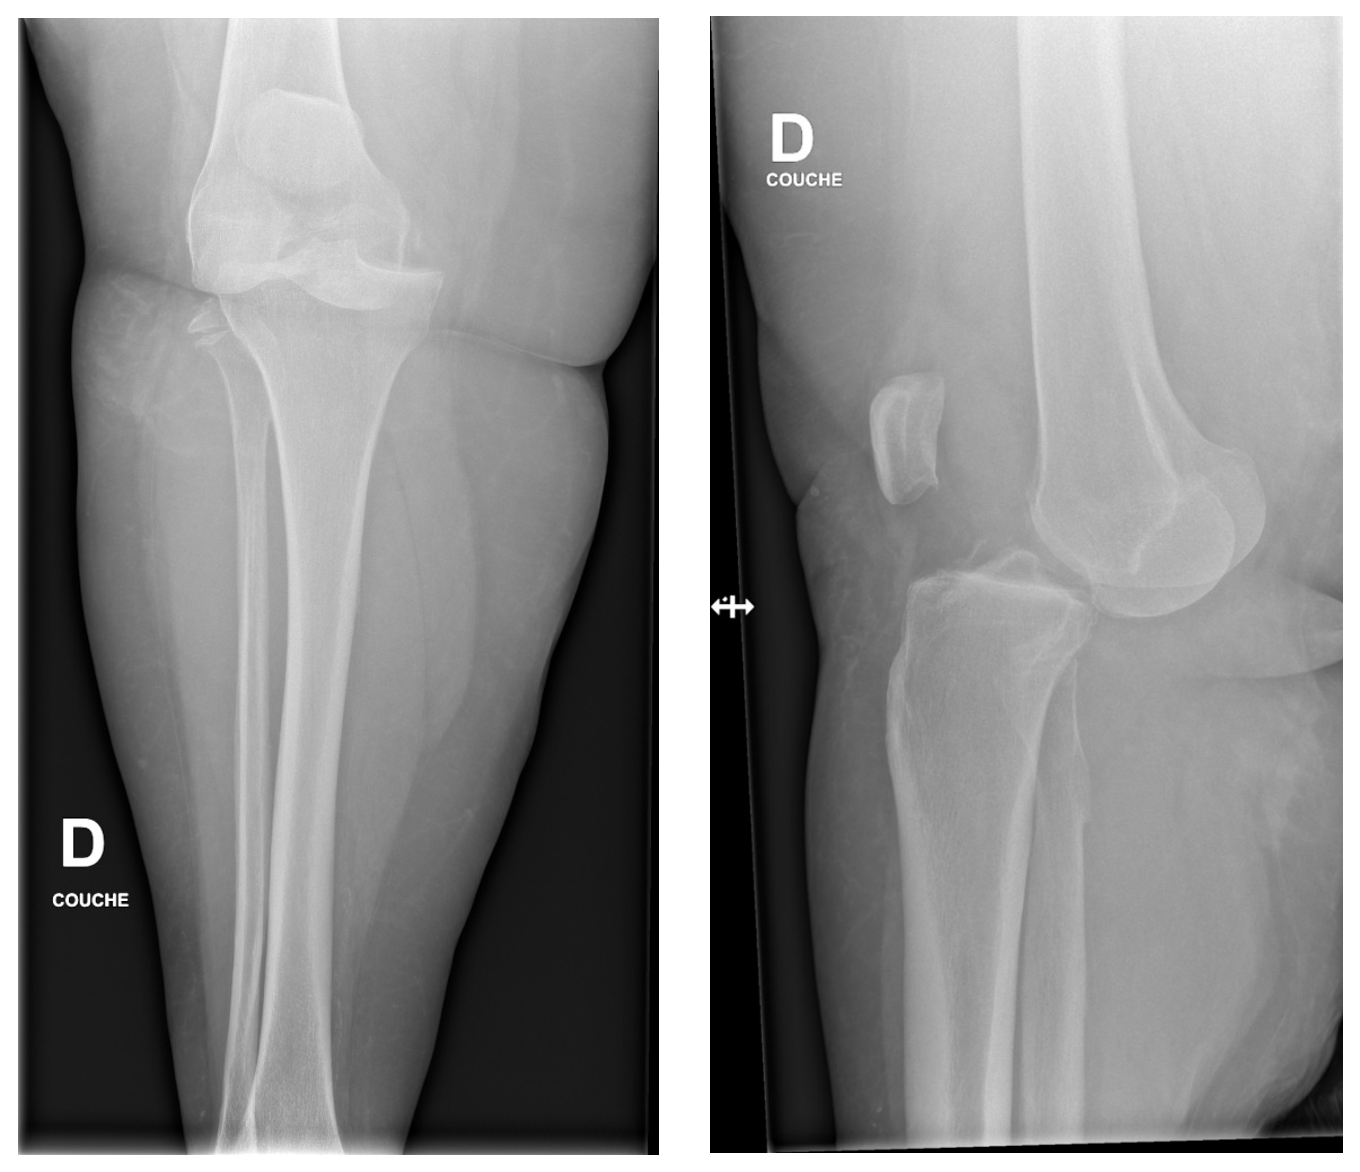

Les radiographies montrent une luxation antérieure du genou avant et après réduction.

Il existe 5 types de luxation, définie par le déplacement du tibia par rapport au fémur : postérieur, antérieur, médial, latéral, et rotatoire. Les luxations antérieures et postérieures sont les plus fréquentes.